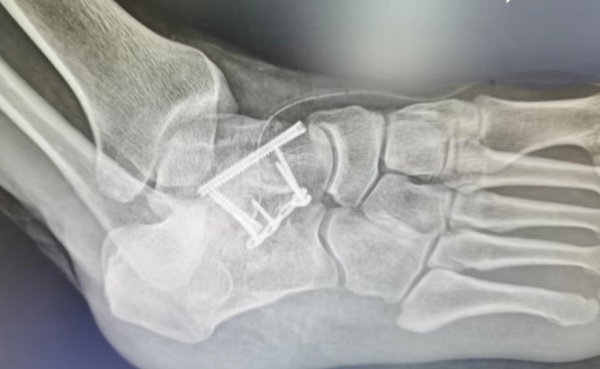

周先生骨折部位。

“整个距骨已经断裂翻转了。”据周先生主治医生雷波介绍,周先生受伤的部位为距骨。距骨是足部活动的主要负重骨之一。由于距骨血供相对较差,骨折后常易发生局部供血障碍、骨折愈合不良,严重者可能导致距骨缺血坏死。因此距骨骨折后,即使完全没有移位,在临床上都建议进行适当的固定,而周先生的距骨骨折已经移位翻转,必须进行手术复位牢固固定。

但由于周先生患脚肿胀非常厉害,出现大面积红水泡,而且外敷了药物,强行手术有感染风险,不得不等待消肿。据雷波医生解释,肢体受到较为严重的伤害,如骨折或挤压伤,局部高度肿胀会形成张力性水泡。此时局部水肿严重,手术会增加皮肤坏死和感染风险。经过进行治疗和护理,周先生右脚消肿,近日顺利进行了手术。